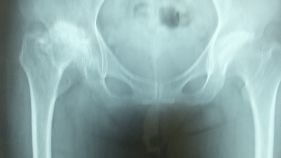

股関節のレントゲン画像

…変形性関節症の程度が確認できます

X線

- 臼蓋が形成されているかどうか・・・臼蓋形成不全の有無

- 大腿骨頭と臼蓋の間隙について・・・重なって見える場合は重症

- シェントン線などがスムーズなラインを描くかどうか・・・大腿骨頭の変形の有無、臼蓋形成不全について

- 大腿骨頭の変形・・・骨端すべり症、大腿骨頭壊死などの有無